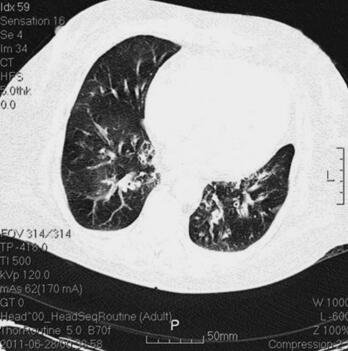

体格检查:P 85次/分,R 12次/分(机械通气),BP 121/61mmHg(多巴胺针剂维持下),T 37.3℃,SPO2 98%。神志清,精神差,气管居中,口插管在位,机械通气,颈静脉无怒张,桶状胸,两肺呼吸音粗,可闻及大量湿啰音及干啰音,心率85次/分,窦性,律齐,双下肢无明显水肿。辅助检查:胸部CT(6月28日)(图1):两肺感染性病变,两下肺支气管扩张症伴感染。心电图(6月28日):窦性心律,T波改变。血常规(6月28日):WBC 13.5×109/L,N 66.3%,Hb 145g/L;CRP(6月28日)3.8mg/L,PCT(6月28日)5.49ng/ml。

图1 胸部CT(6月28日):两肺感染性病变,两下肺支气管扩张症伴感染